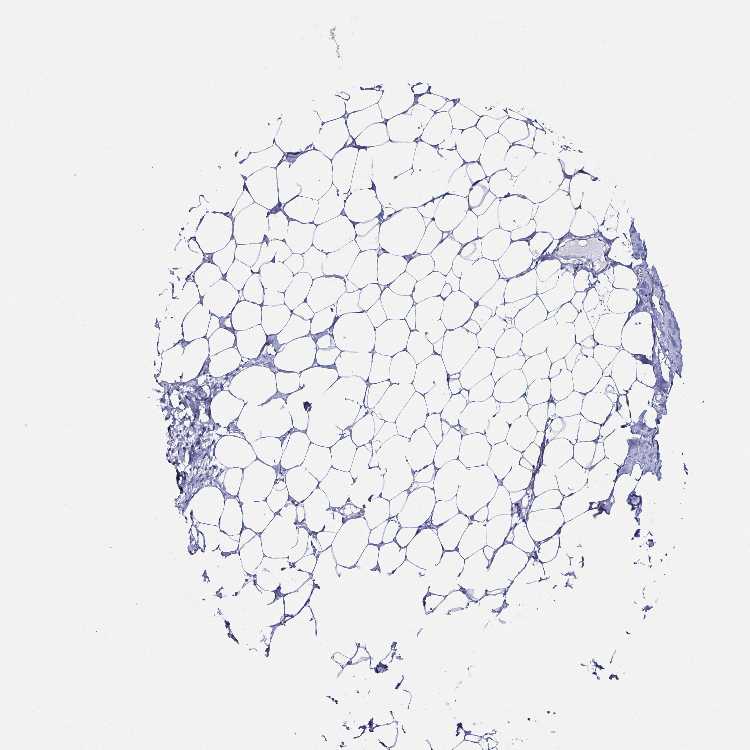

BREAST - Antibody stainingi

Antibody staining in the annotated cell types in the current human tissue is reported as not detected, low, medium, or high, based on conventional immunohistochemistry profiling in selected tissues. This score is based on the combination of the staining intensity and fraction of stained cells.

Each image is clickable and will lead to virtual microscopy that enables deeper exploration of all samples and also displays staining intensity scores, fraction scores and subcellular localization as well as patient and tissue information for each sample.

Antibody HPA034881Antibody CAB002154

Adipocytes Not detectedNot detected

Glandular cells Not detectedNot detected

Myoepithelial cells Not detectedNot detected